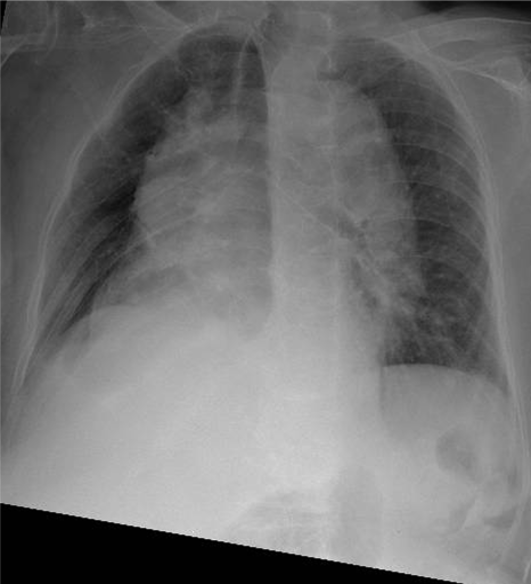

Hãy phân tích tình huống Nữ 95 tuổi

1-Khí quản lệch (P) 2-Đóng vôi sụn khí phế quản 3-Phình động mạch chủ ngực đoạn lên